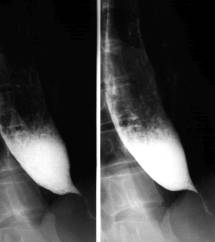

Achalazie

Achalazia este o stare de permanenta contractie a cardiei care produce dilatarea esofagului supraiacent. Stagnarea alimentelor la nivelul esofagului determina un proces inflamator al mucoasei cu lichid de staza. Aceasta poate produce o aspirare traheala a continutului esofagian, ceea ce induce modificari inflamatorii cronice de tip alveolar sau interstitial.

Imagistic la examenul cu bariu cardia apare mult īngustata cu contururi bine delimitate, netede, cu pliuri paralele, centreaza segmentul supraiacent. Esofagul toracic este dilatat īn grade variabile uneori foarte mult si depasind contururile mediastinului.

Concomitent esofagul se alungeste si se cudeaza. Undele peristaltice initial sunt frecvente, profunde, dar ineficiente. Evacuarea este lenta īn cantitate mica.